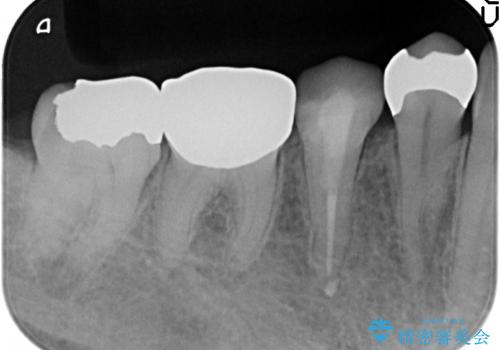

- 右下奥の歯茎がたまに腫れて膿が出るので診て欲しいといらっしゃった方の症例です。

診査の結果右下6の歯の神経が死んでいたため根管治療を行い、オールセラミッククラウンによる補綴を行いました。